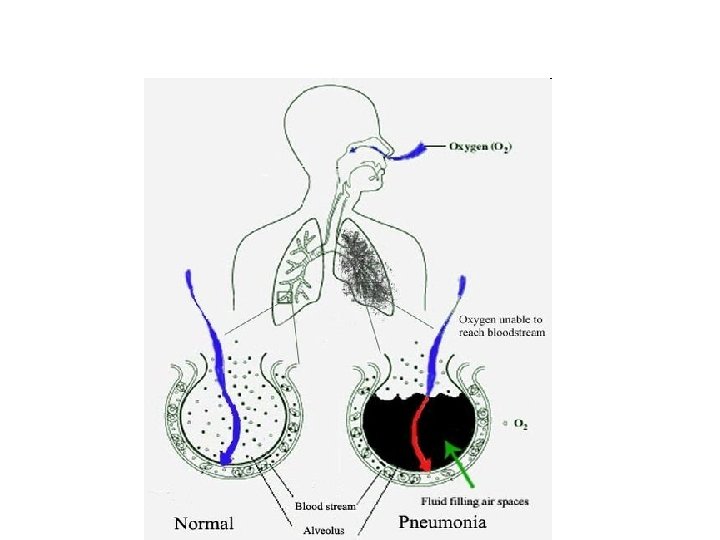

What is Pneumonia? • Pneumonia is an inflammatory condition of the lung • characterized by inflammation of the parenchyma of the lung (alveoli) • Abnormal alveolar filling with fluid causing Air space disease (consolidation and exudation)

Pathogenesis • Inhalation, aspiration and hematogenous spread are the 3 main mechanisms by which bacteria reaches the lungs • Primary inhalation: when organisms bypass normal respiratory defense mechanisms or when the Pt inhales organisms that colonize the upper respiratory tract or respiratory support equipment

Pathogenesis • Aspiration: occurs when the Pt aspirates colonized upper respiratory tract secretions – Stomach: reservoir of GNR that can ascend, colonizing the respiratory tract. • Hematogenous: originate from a distant source and reach the lungs via the blood stream.

Pathogenesis • • • Microaspiration from nasopharynx: S. Pneumonia Inhalation: TB, viruses, Legionella Aspiration: anaerobes Bloodborne: Staph endocarditis, septic emboli Direct extension: trauma